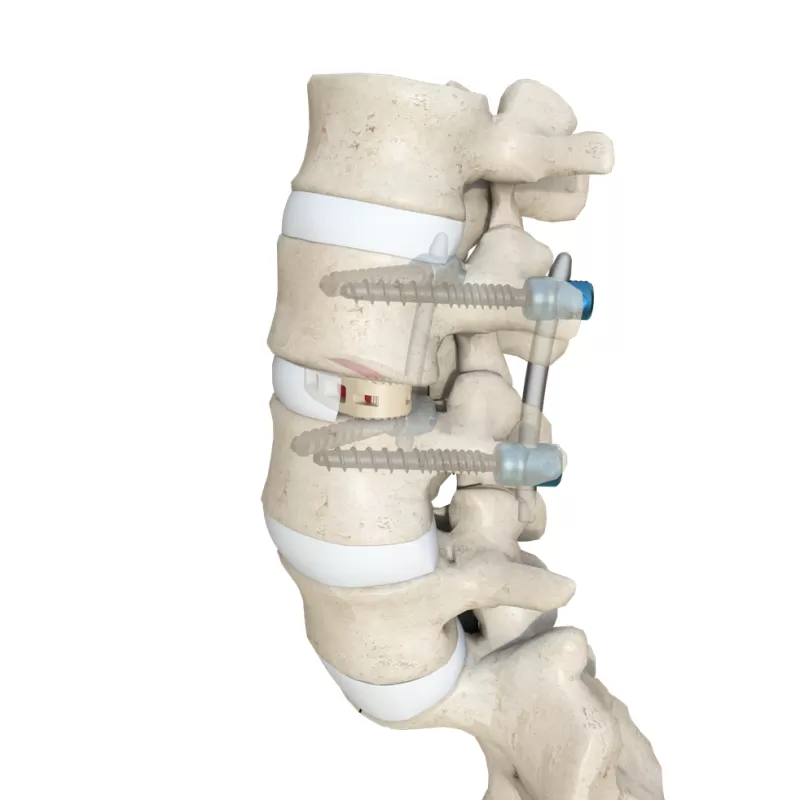

- Standalone Lumbar Interbody Fusion Cage

- Lumbar Interbody Fusion Cage

- Ti Posterior Thoracolumbar Rod-Screw System(5.5)

- Ti Posterior Thoracolumbar Rod-Screw System(6.0)

- Thoracolumbar Rod System MIS

- The Next Evolution Luna Posterior Thoracolumbar Spinal System